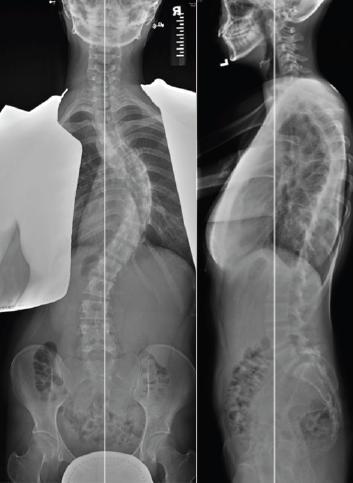

Surgery: (Figs. 8-10) For the very small number of children with severe curves, internal fixation is applied to the spine to correct the curve within the limits of safety. Surgery for scoliosis has been made very safe by major advances in surgical techniques including surgical navigation and the use of intraoperative spinal cord monitoring [1,6,7,8].

![]() Fig. 8 AP and Lateral radiograph showing right thoracic curve before surgery. |

![]() Fig. 9 Posterior spinal fusion with thoracic pedicle screws. Note spontaneous correction of compensatory lumbar curve. Lumbar spine motion is preserved. |